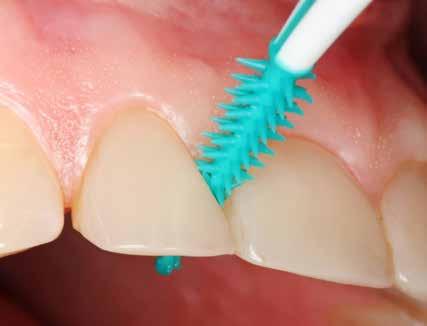

TEGELBERG P, ÓLAFSSON VG, BOGREN A, DAMGAARD C, WIGEN TI Hvilken rolle spiller tandtråd, tandstikkere og interdentalbørster ved approksimal rengøring? / 44

Fælles for alle disse behandlingstrin er, at det terapeutiske mål er biofilmkontrol. Selvom der aktuelt ikke findes validerede biofilmrelaterede udfaldsmål (se nedenfor), giver den trinvise tilgang klinikeren mulighed for at iværksætte de nødvendige behandlinger og undgå overbehandling. Det er veldokumenteret, at områder med inflammation og kun let fordybede pocher kan holdes i ave med omhyggelig mundhygiejne, dvs. trin 1-terapi (15,16). Det vigtigste redskab til approksimal rengøring er interdentalbørster, mens såvel manuelle som elektriske tandbørster kan anbefales til plakfjernelse på de øvrige tandflader (1). Studier tyder på, at elektriske tandbørster fjerner plakken mere effektivt på voksenbefolkningen som helhed (17), mens de tilsyneladende ikke er bedre end manuelle børster, når det drejer sig om patienter, der har gennemgået en grundig parodontalbehandling.